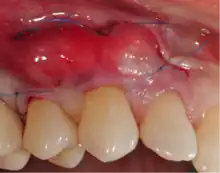

Gingival grafting, also called gum grafting or periodontal plastic surgery,[1][2][3] is a generic term for the performance of any of a number of periodontal surgical procedures in which the gum tissue is grafted. The aim may be to cover exposed root surfaces or merely to augment the band of keratinized tissue.

Exposure of the tooth root due to loss of keratinized tissue around the neck of a tooth is referred to as gingival recession. This can result in sensitivity or pain from the exposed tooth root surface (dentin is more permeable and soft compared to enamel and dentin is what makes up the tooth root).[7] Recession may also cause an unasthetic appearance especially if located in the anterior dentition (front teeth). While not all cases of gingival recession require surgical correction, there are various options if that is what the patient desires.[8] It should be reinforced that recession left untreated will not result in tooth loss, contrary to popular belief. Also, recession that is left untreated can be maintained and the inflammation kept at bay with proper brushing and oral hygiene technique.[5] On the other hand, if one desires to pursue corrective therapy, there are a wide variety of techniques ranging from autograft (your own tissue, usually taken from the palate), allograft (someone else's tissue, cadaver), xenograft (animal, usually porcine or bovine) or simply repositioning of the tissue native to the site.[9] The benefits of corrective therapy often result in decreased sensitivity through coverage of the root surface in addition to a gain in the keratinized tissue mentioned beforehand.

Gum grafting, also known as a gingival graft or periodontal plastic surgery, is a surgical procedure to reverse gum recession. Gum recession exposes the roots of teeth,[10] which can lead to sensitivity and put teeth at a higher risk of damage or disease[11] due to the loosening of their attachment within the gums and bones of the jaw. Should gum recession continue, bone and keratinized tissue will be at greater risk of being damaged and permanently lost around the teeth. The aim of a gum graft is to extend keratinized tissue of the gums to cover tooth roots,[12] which restores their firm placement within the jaw and prevents further damage.